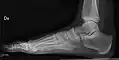

- Ankle - AP/Mortice and Lateral

-

Ankle - frontal -

15 degrees internal rotation -

Lateral (this one a bit suboptimal by not seeing straight through the ankle joint) -

Lateral oblique (to visualize the posterior border of the tibia)

- Calcaneum - Axial and Lateral

- Foot / Toes - Dorsoplantar, Oblique and Lateral.[19]